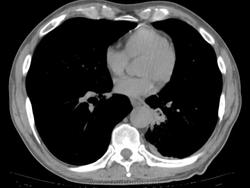

КТ:

Добавила КТ в начале случая. Контрастирования не было, не будет. Дайком тут: http://files.mail.ru/0KS7TD   22,3 МБ объём

По всей видимости аномалия развития, связанная с нижней долей слева по типу гипоплазии-недоразвития.

Сейчас и на рентгенограмме левый корень выглядит ущербно недоразвитым в области тела и хвоста, да и обнажение части грудного отдела позвоночника справа моежт быть объяснимо.

Выставила интралобарную секвестрацию. Пациент консультирован в областном центре, дополнительных методов обследований там не выполнялось, посмотрели дайком нативной КТ ОГК и согласились.

При просмотре ФЛГ видела кисты/буллы и ненормальный левый корень. Полосу за тенью сердца приняла за шварту. Взяла на КТ, чтоб разобраться, связан ли куцый корень и кисты. Секвестрация оказалась сюрпризом. Решила, что всё-таки аномалия со своей плеврой. Насколько смогла разобраться на нативном исследовании, все бронхи на месте, а дополнительное образование с кистами и каким-то зачатком бронхиальной системы - ниже S6 и медиальнее S10. С темой секвестрации знакома по детским случаям коллег.

Для доказательства надо бы контрастировать, найти артерию, питающую секвестр от аорты и дренирующую вену. Но по административным причинам контрастирование не проводилось. Со слов пациента, хроническими пневмониями не страдает.